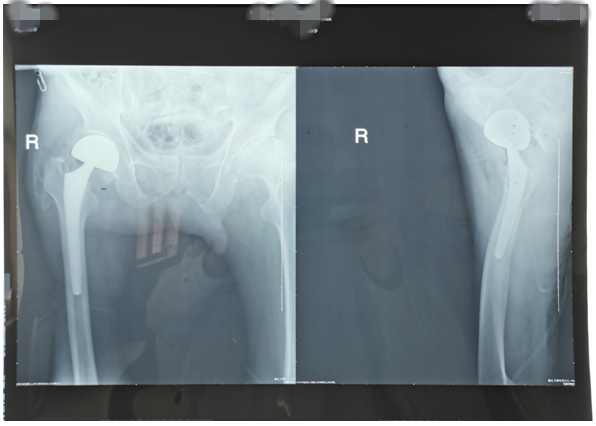

近期,我科又為兩位高齡老人因股骨頸骨折行髖關(guān)節(jié)置換術(shù)。一位是呂大爺,82歲高齡,右髖部外傷后疼痛一個(gè)月就診。當(dāng)時(shí)呂大爺外傷后局部疼痛,未引起注意仍日常活動(dòng),癥狀逐漸加重后就診,既往有高血壓、腦梗塞、腦出血病史,入院后積極完善術(shù)前評(píng)估,在無(wú)絕對(duì)手術(shù)禁忌癥時(shí)行右側(cè)股骨頸骨折髖置換術(shù),手術(shù)時(shí)間短,出血少,術(shù)后第二天呂大爺扶助步器下床活動(dòng),避免了因骨折長(zhǎng)時(shí)間臥床各種并發(fā)癥的發(fā)生,老人及家屬對(duì)我們的治療非常滿意。(見下圖)

右髖正側(cè)位手術(shù)前后對(duì)比圖